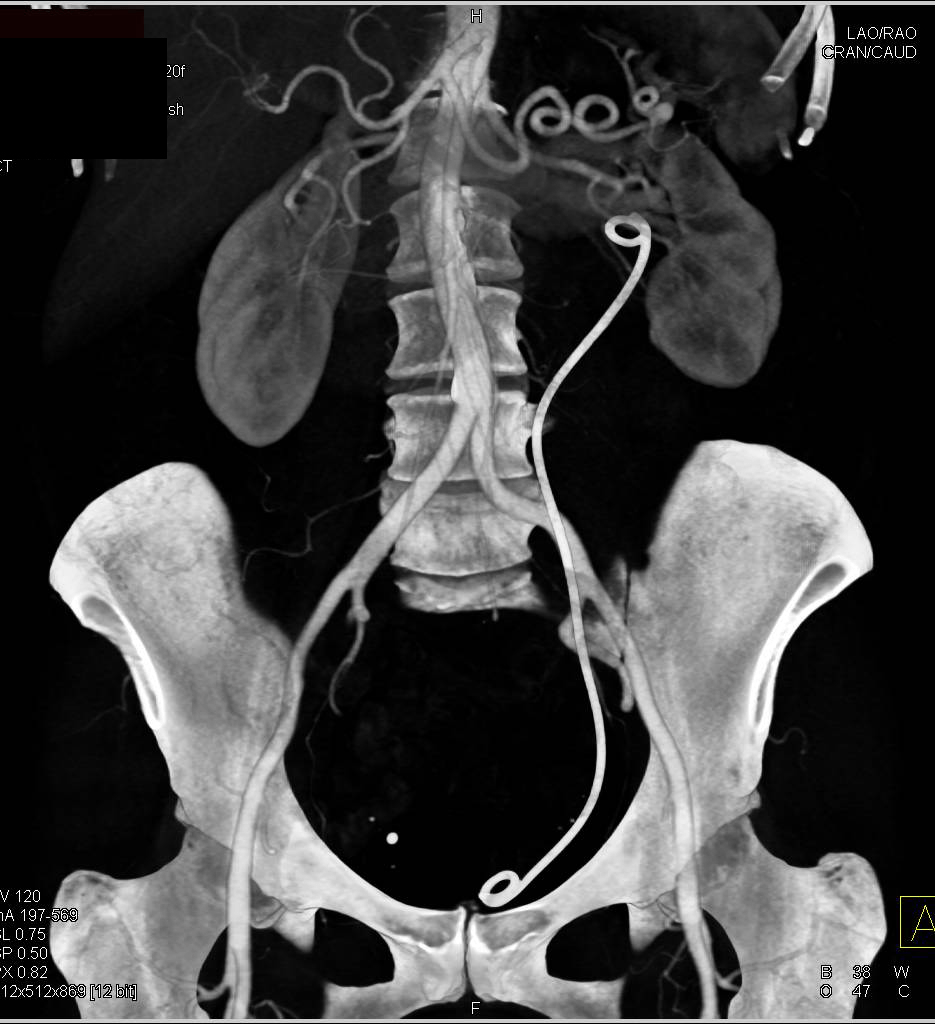

Hekimoglu, A., Ergun, O. and Hekimoglu, B. (2023). Selective Transarterial Embolization for Intractable Hematuria Due to Bladder Carcinomas: A Single-Center Experience. Urology Research & Practice, 49(5), pp.334–337. doi:https://doi.org/10.5152/tud.2023.22224.

Taha, D.-E., Shokeir, A.A. and Aboumarzouk, O.A. (2018). Selective embolisation for intractable bladder haemorrhages: A systematic review of the literature. Arab Journal of Urology, 16(2), pp.197–205. doi:https://doi.org/10.1016/j.aju.2018.01.004.